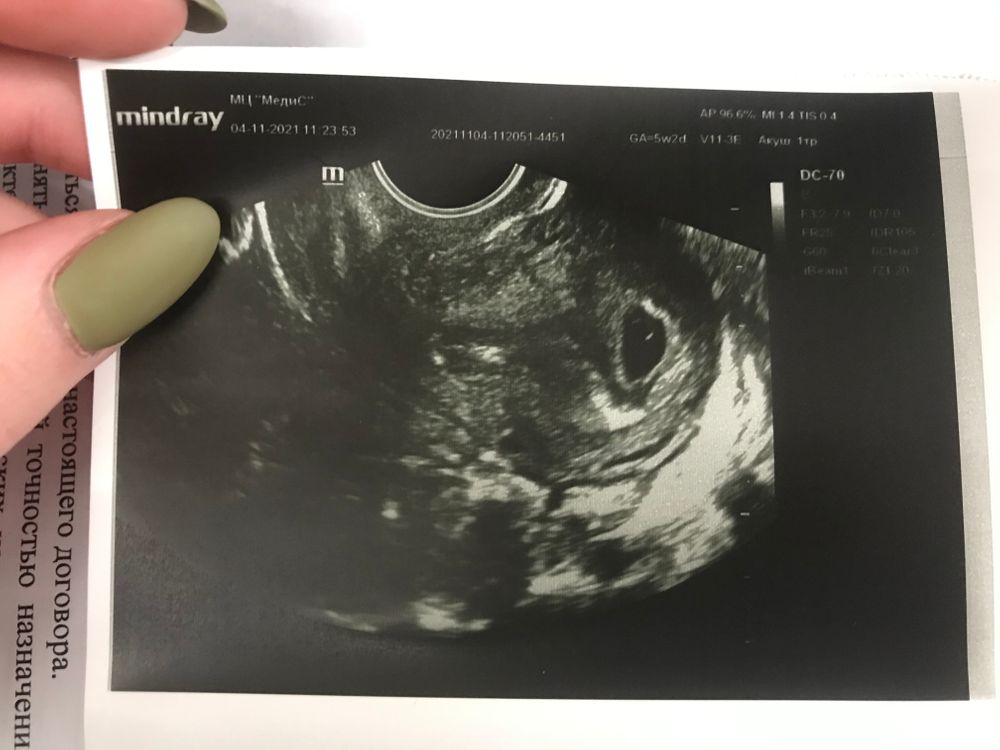

Ksenia, здравствуйте , сегодня поставили ровно 5 неделек

Яна , здравствуйте , УЗИ первое , от М срок 5 неделек , сердечко смогу услышать только через неделю - две

Беременность 6 недель Беременна)